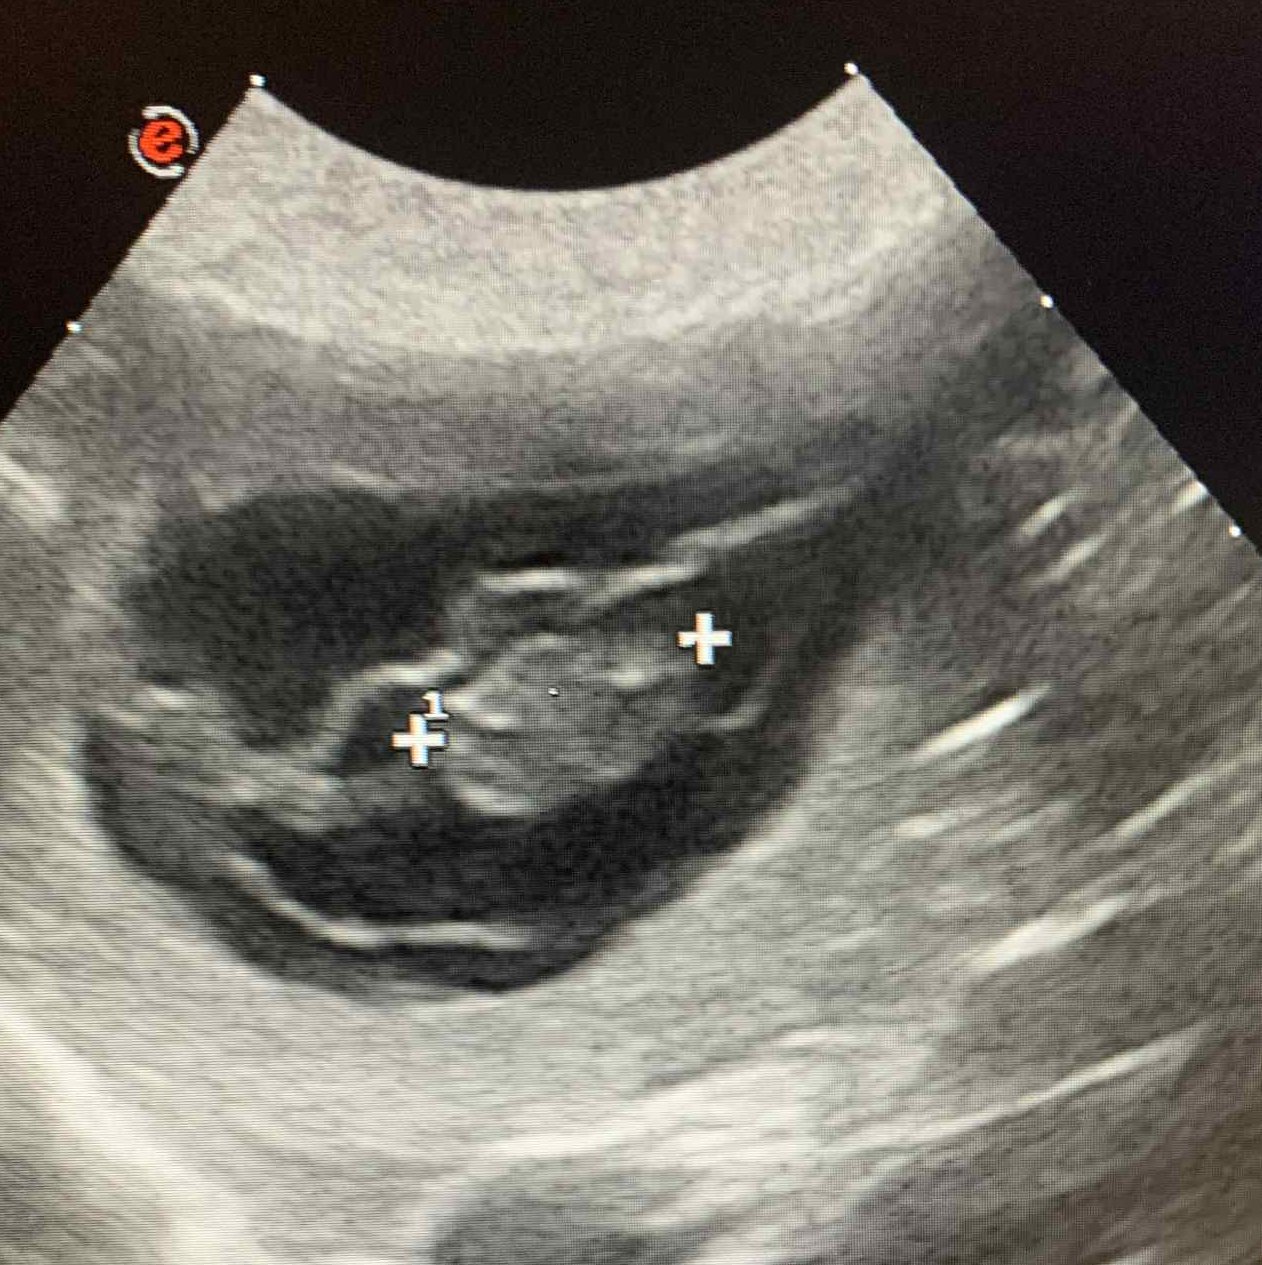

Březost Ziry potvrzena!

Ultrazvuk ukázal minimálně 4 štěňátka a my se moc těšíme!